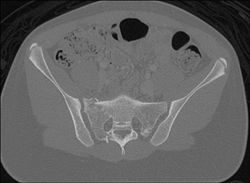

DIEP Flap Planning